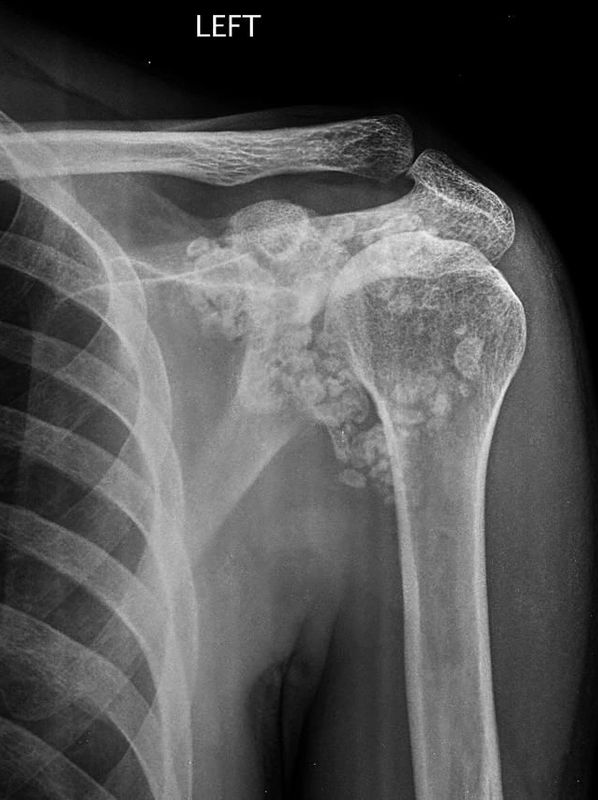

Day 1 will start with a review of calcific tendinopathy (simple to challenging cases), how to treat for best outcomes and multidisciplinary care. This will lead into a deeper look at shoulder disorders on imaging including plain film, US, CT and MRI.

TOPIC 11 - CALCIFIC TENDINOPATHY

TOPIC 12 - UNDERSTANDING IMAGING - PEARLS & PITFALLS

Case Studies & Discussion

A patient is referred to you for severe right shoulder pain of 2 weeks. She complains of regular night pain, difficulty with arm movement and no prior history of shoulder disorders. No trauma, minimal improvement with physiotherapy in her community, a recent flare with massage and no effect of regular OTC NSAID use. Right dominant.

Examination reveals difficulty in early movement, particularly flexion and abduction (limited to 30 deg). Muscle power around the shoulder is reduced 4-/5 in elbow flexion, abduction, IR and ER, limited by pain. Special tests are limited. No muscle loss around the scapula. She is tender to palpation over the ACJ and subacromially. Passive movement in ER is moderately restricted (50.70,90 throughout standard abduction points), with GHJ abd to 80 deg.